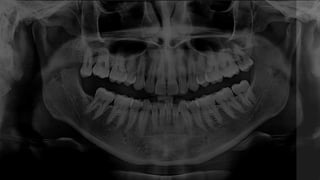

LA PARTE SUPERIOR DE ESTE HUESO VA A FORMAR EL

PISO DE LAS CAVIDADES NASALES Y ÓRBITAS.

LA PARTE INFERIOR DEL HUESO MAXILAR SUPERIOR

FORMA PARTE DEL PALADAR Y LAS CRESTAS ALVEOLARES

QUE SOSTIENEN A LOS DIENTES.

EL CUERPO DE ESTE HUESO INTERIORMENTE SE

ENCUENTRA EL SENO MAXILAR

ES IMPAR Y ESTÁ UBICADO EN LA LÍNEA MEDIA. ES EL

ÚNICO HUESO MÓVIL DE LA CARA. SU CUERPO ES

CÓNCAVO HACIA ATRÁS Y SUS RAMAS SE DIRIGEN

HACIA ARRIBA.

LA PARTE SUPERIORDE ESTE HUESO VA A FORMAR EL PISO DE LAS CAVIDADES NASALES Y ÓRBITAS. LA PARTE INFERIOR DEL HUESO MAXILAR SUPERIOR FORMA PARTE DEL PALADAR Y LAS CRESTAS ALVEOLARES QUE SOSTIENEN A LOS DIENTES. EL CUERPO DE ESTE HUESO INTERIORMENTE SE ENCUENTRA EL SENO MAXILAR

ES IMPAR YESTÁ UBICADO EN LA LÍNEA MEDIA. ES EL ÚNICO HUESO MÓVIL DE LA CARA. SU CUERPO ES CÓNCAVO HACIA ATRÁS Y SUS RAMAS SE DIRIGEN HACIA ARRIBA.